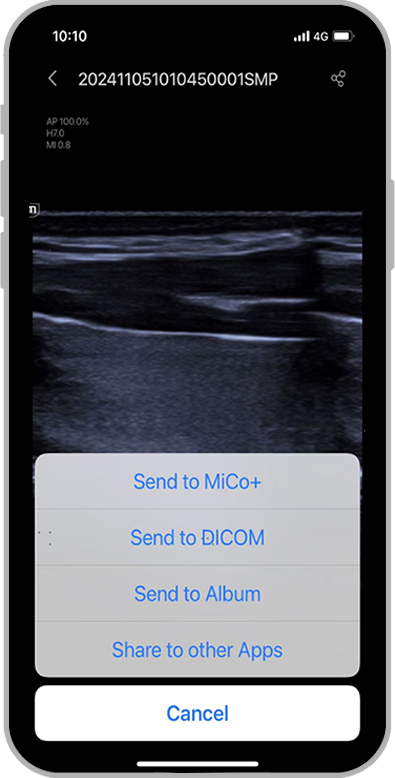

3Biedt oplossingen voor beheer van pati?ntgegevens

4Voltooit uw workflow door naadloze interconnectiviteit met uw informatiesysteem

3Biedt oplossingen voor beheer van pati?ntgegevens

4Voltooit uw workflow door naadloze interconnectiviteit met uw informatiesysteem